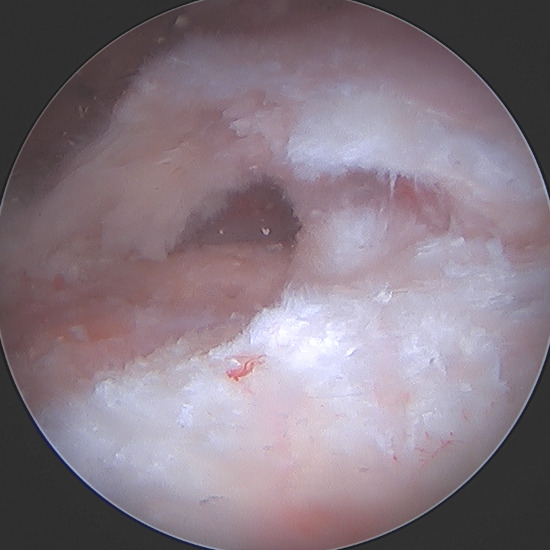

For the primary repair, a double row repair was completed. Medial anchor placement and fixation needed special consideration due to poor bone quality as a result of the subchondral cyst. To support anchor fixation, a calcium phosphate substitute (Tactoset® by Anika Therapeutics) was injected under direct visualization into the subchondral cyst and allowed to set for approximately 10 minutes. One triple-loaded medial row anchor (Healix Advance™ with Dynacord™ by DePuy Synthes) was then placed into the greater tuberosity. Six sutures were passed through the rotator cuff and tied in standard arthroscopic fashion after which two lateral row anchors (X-Twist™ by Anika Therapeutics) were placed to complete a double-row fixation of the rotator cuff tear.

Due to the delaminated nature of the tear and active work as a laborer, biologic augmentation (TAPESTRY® Biointegrative Implant by Embody) was added to support tendon healing. This biologic augmentation was chosen due to the delamination and retraction of the rotator cuff as an increased change of retear is noted when present. The arthroscopic introducer was used from the lateral portal via the cannula. Once appropriately positioned over the delaminated area, three bioabsorbable anchors were used to fixate the implant in the tendon and bone, with two anchors placed medially in the soft tissue and two anchors placed laterally into bone.